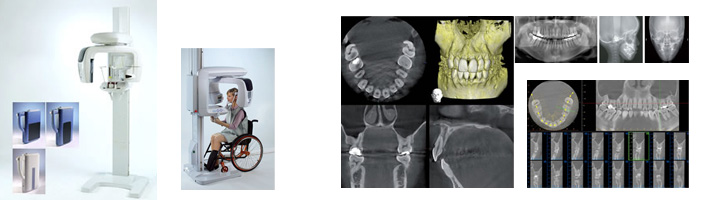

矯正治療は、治療計画をしっかり立てるために、起こりうるリスクを把握し、精密な検査・診断を行うことが非常に重要です。長嶺南ファミリー歯科では、歯だけではなく、矯正診断に欠かせないCTやセファロ、高機能3Dシミュレーションソフトを導入しており、精度の高いデータに基づき、適切な治療方針を立て、一歩先を行く質の高い矯正治療を提供しています。

セファログラム(頭部X線規格写真)・CT

世界共通の規格写真で、イヤーロッドと呼ばれる突起を耳の穴に入れて位置合わせすることによって、頭部を同じ位置・拡大率で撮影することができます。

それにより、矯正治療前の診断時、矯正治療中や治療後の写真を同じ規格で撮影でき、比較することが可能となります。

このセファロ(頭部X線規格写真)を用いた分析は、矯正治療においては非常に重要で、当院でもセファロを導入しております。

難しくてイメージが湧きにくいかもしれませんが、当院では治療開始前に分析結果のご説明をしております。

当院ではコンピュータ断層撮影(Computed Tomography 略:CT)機械を完備しています。

レントゲン撮影では2次元の情報しか得ることができませんが、CT撮影をすることで3次元の多くの情報を得ることができます。

矯正歯科だけでなく、インプラントの患者さんにも安心な診断をすることが可能になりました。